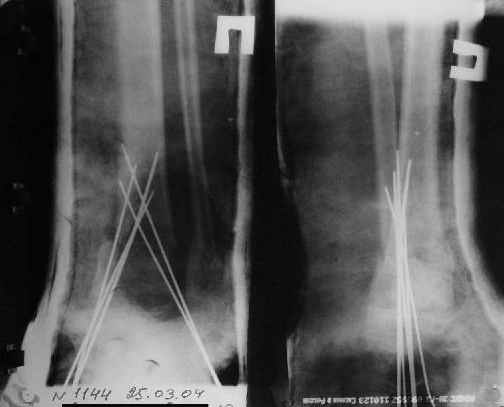

Нашел в комп-ре схожий случай:

1) з/репозиция, 2) фиксация 2 спицами, 3) аппарат, 4) фиксационные

спицы удалены...

См. аттачт.

А можно было наложить аппарат и по поводу ложного сустава...

По крайней мере не было бы укорочения (пусть и в 2 см)...